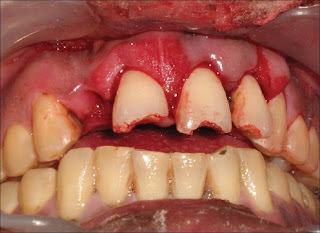

The patient was a healthy, 42-year-old male (Figure 1) who had suffered a roadside accident 2 h before and after initial examination and soft tissue management, he was referred to the conservative Dentistry PG Clinics of Dr. R. Ahmed Dental College and Hospital by Oral Surgery Department of the same college Clinical examination revealed that the injury had resulted in 5-6 mm intrusion (Figure 2) and uncomplicated crown fracture of maxillary permanent central incisors and left lateral incisor (Figure 3) .

Figure 2: Intra-oral view showing intruded upper central incisors and left lateral incisors, with loss of upper right lateral incisor